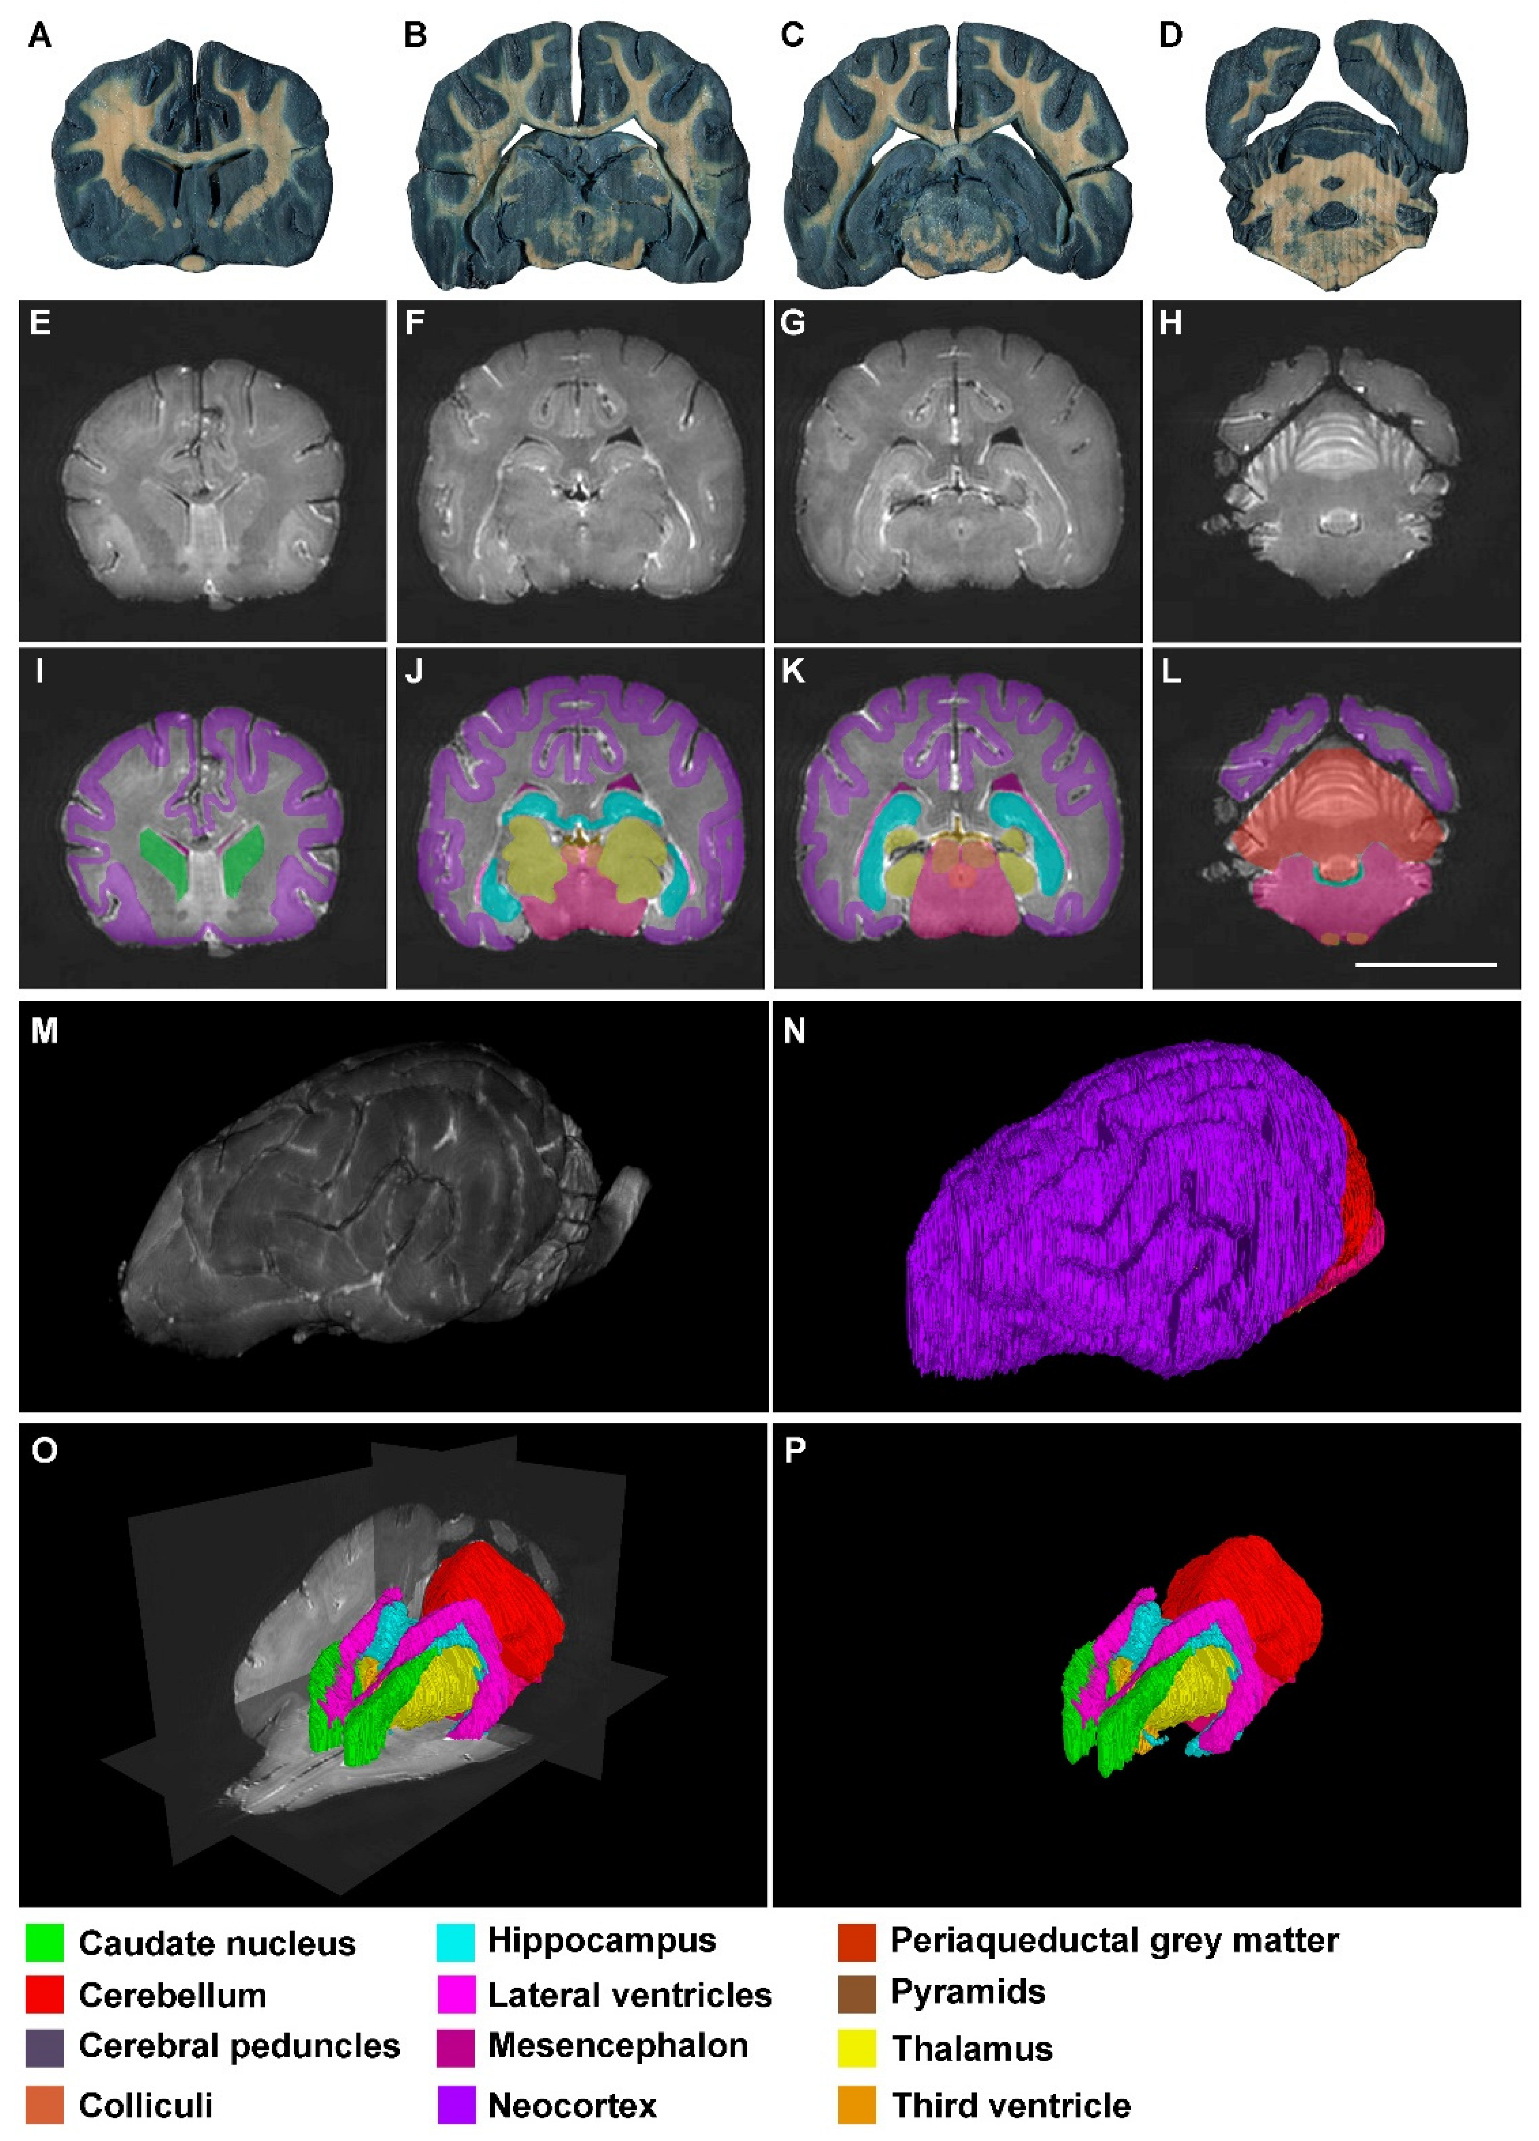

3. Results